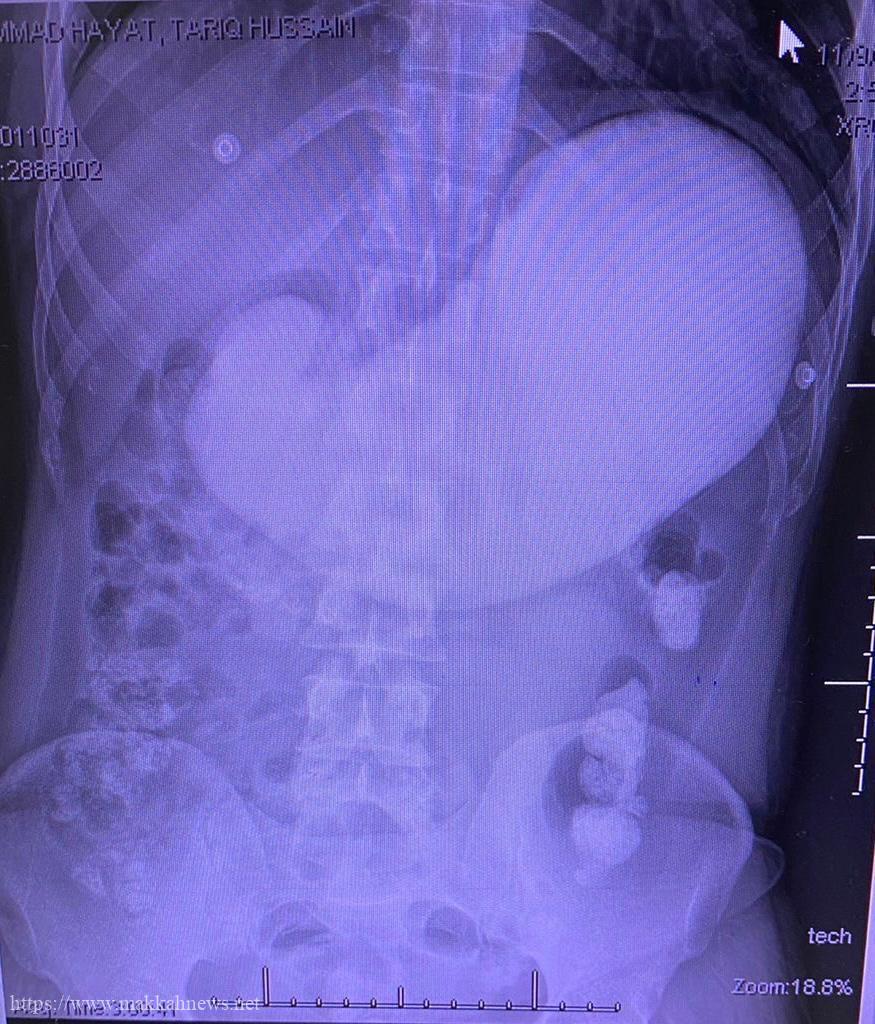

تدخل جراحي عاجل .. ينقذ عامل حاول الإنتحار ببلع ” خليط اسمنتي ” بجدة

جدة : نجح طاقم طبي و فني بمستشفى الملك عبد العزيز بجدة من إنقاذ مريض باكستاني الجنسية في الثلاثين من…